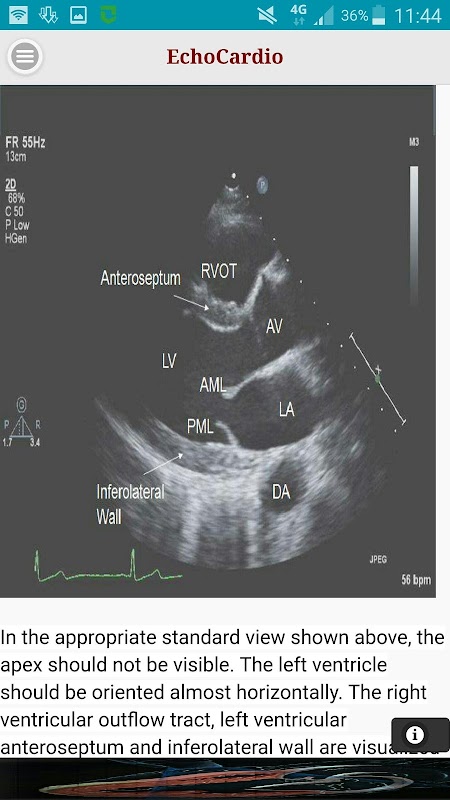

Parasternale asse corto